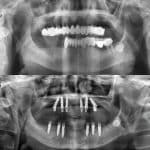

- İmplant üstü protez olarak da kaplama uygulanabilir.